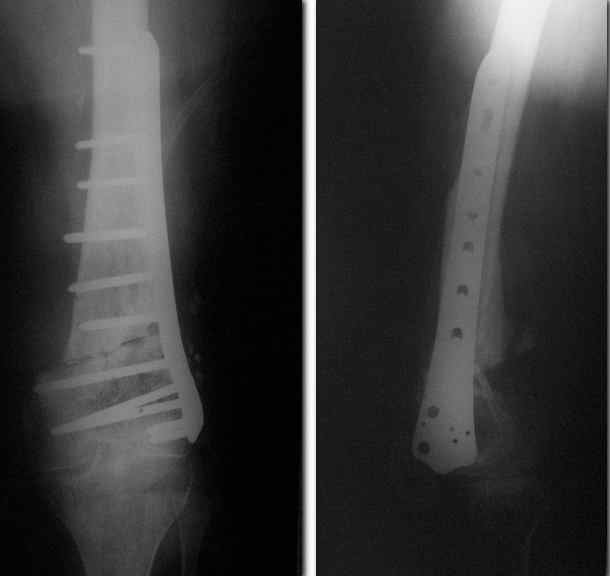

Re: Ложный сустав

Спасибо. Прооперировали во вторник.

Выглядит красиво. А движения в колене какие были на столе?

Была контрактура и спаянный с суставной поверхностью надколенник. Сделали до синтеза редрессацию. Достигли почти полного объема движений.